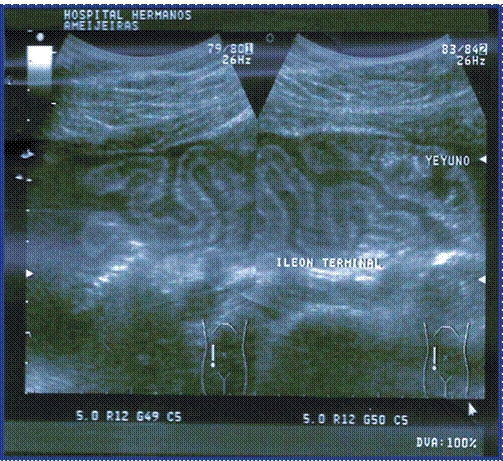

Los estudios imagenológicos reportaron radiografía de tórax sin alteraciones, ultrasonido abdominal que informa líquido libre en cavidad (fig.1), pero llamó la atención la existencia de asas intestinales delgadas (duodeno y yeyuno), ligeramente distendidas con líquido en su interior y pobre peristalsis observándose íleon terminal rígido, de aspecto inflamatorio a descartar ileítis regional (Figura. 2), duodeno engrosado con aspecto inflamatorio del patrón mucoso con sospecha de úlcera en segunda porción, el resto sin alteraciones. (Figura 1 y 2).